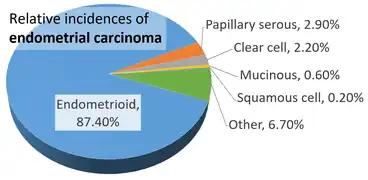

Approximately 40% of cases are related to obesity.[3] Endometrial cancer is also associated with excessive estrogen exposure, high blood pressure and diabetes.[1] Whereas taking estrogen alone increases the risk of endometrial cancer, taking both estrogen and a progestogen in combination, as in most birth control pills, decreases the risk.[1][3] Between two and five percent of cases are related to genes inherited from the parents.[3] Endometrial cancer is sometimes loosely referred to as "uterine cancer", although it is distinct from other forms of uterine cancer such as cervical cancer, uterine sarcoma, and trophoblastic disease.[9] The most frequent type of endometrial cancer is endometrioid carcinoma, which accounts for more than 80% of cases.[3] Endometrial cancer is commonly diagnosed by endometrial biopsy or by taking samples during a procedure known as dilation and curettage.[1] A pap smear is not typically sufficient to show endometrial cancer.[4] Regular screening in those at normal risk is not called for.[10]

Traditional classification of endometrial carcinomas is based either on clinical and endocrine features (Type I and Type II), or histopathological characteristics (endometrioid, serous, and clear-cell). Some tumors are difficult to classify and have features overlapping more than one category. High grade endometrioid tumors, in particular, tend to have both type I and type II features.[44]

The vast majority of endometrial cancers are carcinomas (usually adenocarcinomas), meaning that they originate from the single layer of epithelial cells that line the endometrium and form the endometrial glands. There are many microscopic subtypes of endometrial carcinoma, but they are broadly organized into two categories, Type I and Type II, based on clinical features and pathogenesis. The two subtypes are genetically distinct.[10]

Type I endometrial carcinomas occur most commonly before and around the time of menopause. In the United States, they are more common in white women, particularly those with a history of endometrial hyperplasia. Type I endometrial cancers are often low-grade, minimally invasive into the underlying uterine wall (myometrium), estrogen-dependent, and have a good outcome with treatment.[10] Type I carcinomas represent 75–90% of endometrial cancer.[15][46]

Type II endometrial carcinomas usually occur in older, post-menopausal people, in the United States are more common in black women, and are not associated with increased exposure to estrogen or a history of endometrial hyperplasia. Type II endometrial cancers are often high-grade, with deep invasion into the underlying uterine wall (myometrium), are of the serous or clear cell type, and carry a poorer prognosis. They can appear to be epithelial ovarian cancer on evaluation of symptoms.[10][46] They tend to present later than Type I tumors and are more aggressive, with a greater risk of relapse and/or metastasis.[15]

Endometrioid adenocarcinoma

In endometrioid adenocarcinoma, the cancer cells grow in patterns reminiscent of normal endometrium, with many new glands formed from columnar epithelium with some abnormal nuclei. Low-grade endometrioid adenocarcinomas have well differentiated cells, have not invaded the myometrium, and are seen alongside endometrial hyperplasia. The tumor's glands form very close together, without the stromal tissue that normally separates them. Higher-grade endometrioid adenocarcinomas have less well-differentiated cells, have more solid sheets of tumor cells no longer organized into glands, and are associated with an atrophied endometrium. There are several subtypes of endometrioid adenocarcinoma with similar prognoses, including villoglandular, secretory, and ciliated cell variants. There is also a subtype characterized by squamous differentiation. Some endometrioid adenocarcinomas have foci of mucinous carcinoma.[47]

Serous carcinoma

Serous carcinoma is a Type II endometrial tumor that makes up 5–10% of diagnosed endometrial cancer and is common in postmenopausal women with atrophied endometrium and black women. Serous endometrial carcinoma is aggressive and often invades the myometrium and metastasizes within the peritoneum (seen as omental caking) or the lymphatic system. Histologically, it appears with many atypical nuclei, papillary structures, and, in contrast to endometrioid adenocarcinomas, rounded cells instead of columnar cells. Roughly 30% of endometrial serous carcinomas also have psammoma bodies.[20][46] Serous carcinomas spread differently than most other endometrial cancers; they can spread outside the uterus without invading the myometrium.[20]

Clear cell carcinoma

Clear cell carcinoma is a Type II endometrial tumor that makes up less than 5% of diagnosed endometrial cancer. Like serous cell carcinoma, it is usually aggressive and carries a poor prognosis. Histologically, it is characterized by the features common to all clear cells: the eponymous clear cytoplasm when H&E stained and visible, distinct cell membranes.[46] The p53 cell signaling system is not active in endometrial clear cell carcinoma.[15] This form of endometrial cancer is more common in postmenopausal women.[20]

Mucinous carcinoma

Mucinous carcinomas are a rare form of endometrial cancer, making up less than 1–2% of all diagnosed endometrial cancer. Mucinous endometrial carcinomas are most often stage I and grade I, giving them a good prognosis. They typically have well-differentiated columnar cells organized into glands with the characteristic mucin in the cytoplasm. Mucinous carcinomas must be differentiated from cervical adenocarcinoma.[47]

Mixed or undifferentiated carcinoma

Mixed carcinomas are those that have both Type I and Type II cells, with one making up at least 10% of the tumor.[47] These include the malignant mixed Müllerian tumor, which derives from endometrial epithelium and has a poor prognosis.[49]

Undifferentiated endometrial carcinomas make up less than 1–2% of diagnosed endometrial cancers. They have a worse prognosis than grade III tumors. Histologically, these tumors show sheets of identical epithelial cells with no identifiable pattern.[47]

Other carcinomas

Non-metastatic squamous cell carcinoma and transitional cell carcinoma are very rare in the endometrium. Squamous cell carcinoma of the endometrium has a poor prognosis.[47] It has been reported fewer than 100 times in the medical literature since its characterization in 1892. For primary squamous cell carcinoma of the endometrium (PSCCE) to be diagnosed, there must be no other primary cancer in the endometrium or cervix and it must not be connected to the cervical epithelium. Because of the rarity of this cancer, there are no guidelines for how it should be treated, nor any typical treatment. The common genetic causes remain uncharacterized.[50] Primary transitional cell carcinomas of the endometrium are even more rare; 16 cases had been reported as of 2008. Its pathophysiology and treatments have not been characterized.[51] Histologically, TCCE resembles endometrioid carcinoma and is distinct from other transitional cell carcinomas.[52]